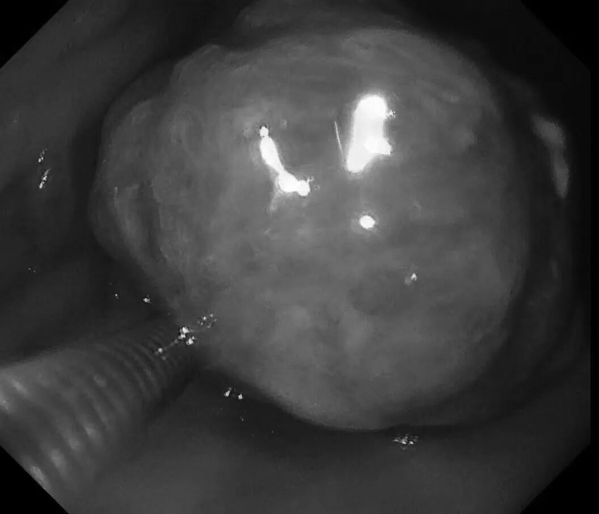

患者王阿姨(化名),65岁。平日里胃肠偶有轻微不适——腹胀,女儿考虑到母亲的年龄,想做个胃早癌筛查,遂带王阿姨来新镜界做胃肠镜精查。

检查中:胃体发现重要异常——胃体巨大息肉,直径约40x40mm!表面充血,带有亚蒂,未来有可能发展为胃癌,健康隐患极大!经与患者家属沟通同意,綦盛麟教授采用ESD(内镜下黏膜剥离术)成功切除巨大息肉。